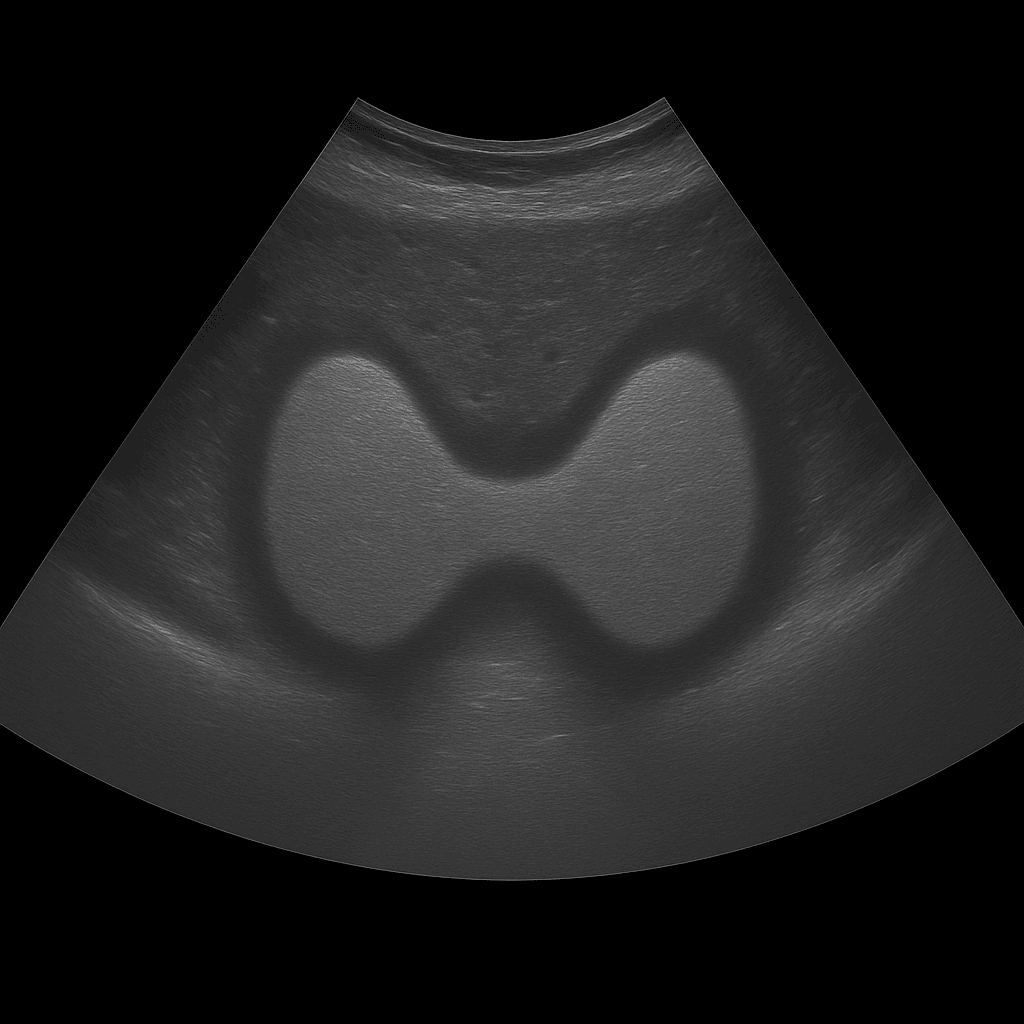

En ultraljudsundersökning av thyroidea eller sköldkörteln används för att bedöma körtelns storlek, form, vävnadsstruktur och eventuella knölar eller cystor. Undersökningen utförs av specialistläkare inom radiologi och ger detaljerade bilder i realtid av sköldkörtelns båda lober samt omgivande vävnader på halsen. Ultraljud thyroidea används som förstahandsmetod vid utredning av knölar, svullnad, förstorad sköldkörtel eller förändrade sköldkörtelprover.

Till skillnad från MR och DT, som sällan används för sköldkörtelns mjukdelar, ger ultraljud en högupplöst och direkt bild av vävnaden. Ultraljud kan också särskilja mellan fasta och vätskefyllda förändringar och används ofta för att vägleda finnålsbiopsi (punktion) vid misstänkta knölar. Det är en snabb, strålningsfri metod som ger ett omedelbart visuellt underlag för diagnos.

Undersökningen utförs medan du ligger på rygg med lätt bakåtböjt huvud för att blottlägga halsområdet. En gel appliceras på huden och läkaren för ultraljudsproben över sköldkörteln. Båda lober och isthmus (förbindelsen mellan loberna) bedöms noggrant i längd- och tvärsnitt. Vid behov kan även närliggande lymfkörtlar på halsen undersökas.